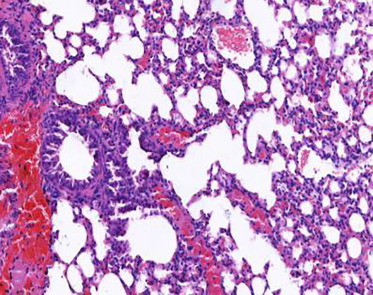

支气管哮喘是一种常见的慢性气道炎性疾病,其特征是长期复发...